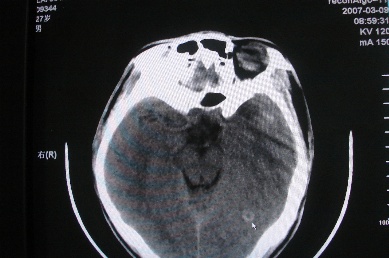

以下是引用zhangzhongshou在2007-4-18 17:49:00的发言:[br]脑实质内多发高密度结节影,支持肉芽肿得诊断,究竟是结核性、真菌性或寄生虫性的需结合临床,进一步检查确诊,但从影像上无法鉴别,只是临床上结核性肉芽肿最为多见而已。